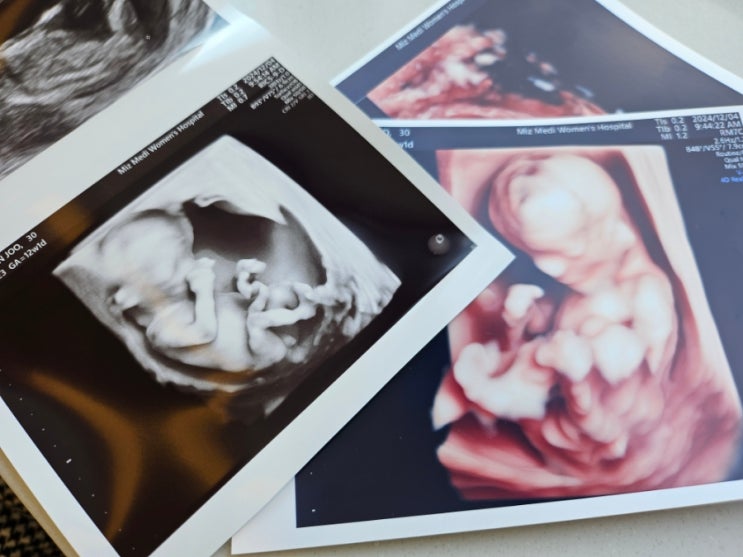

임신 20주차 | 강서미즈메디 중기정밀초음파

임신 20주 6일차 중기정밀초음파 후기 1월에 내 생일도 있고, 설 연휴도 있고 회사도 1년중에 젤 바쁜달이...